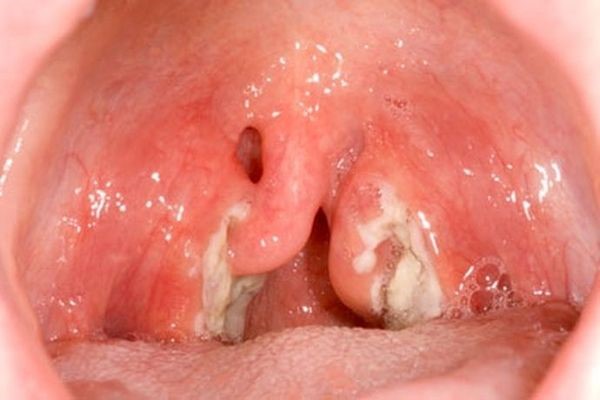

Казеозные пробки в горле представляют собой гнойные образования в результате гибели клеток, лейкоцитов и бактерий. На вид и по консистенции напоминают творог белого, желтого или серого цвета. Заполняют они ниши в миндалинах, называемые лакунами. При внешнем осмотре с помощью зеркала их можно легко увидеть. Иногда они чувствуются при глотании, создавая ощущение инородного предмета в горле.

- Казеозные пробки также являются основным признаком острого тонзиллита (ангины). При фолликулярной и лакунарной ее формах на миндалинах образуется гнойный налет, называемый пробками. Эти пробки и вызывают сильный воспалительный процесс, повышение температуры, общую интоксикацию организма. После комплексного и своевременного лечения (обычно без антибиотиков не обойтись) лакуны очищаются от гнойного налета и человек полностью выздоравливает.

Казеозные пробки, в первую очередь, видны при поверхностном осмотре. Если есть ощущение, что что-то мешает в горле, нужно взять зеркало и заглянуть в ротовую полость. Небольшие бугорки на поверхности небных миндалин с белым или желтоватым содержимым и есть пробки. Чаще всего они появляются при заражении острой формой тонзиллита. Тогда, кроме гнойного налета, будут присутствовать и другие характерные симптомы: